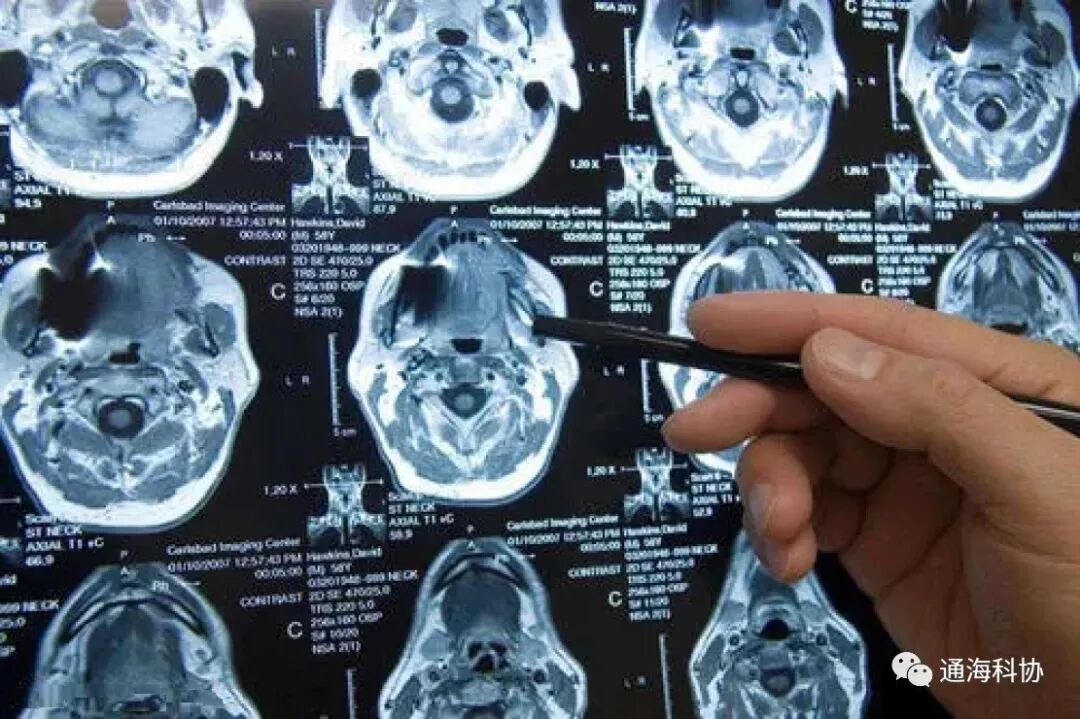

核磁共振成像检查

核磁共振成像检查又称自旋成像,也称磁共振成像,是英文Magnetic Resonance Imaging的译意,简称MRI。核磁共振成像是从原子层面,通过外加梯度磁场检测其物理变化,而绘制出来物体内部结构图像,是一个很复杂的过程,作为科普就不讲得那么深了。

对早期诊断敏感,在一些病变早期时就能够显示出异常,能够早于CT和B超等方法发现问题,比较适宜对头颅、脊髓、骨骼、四肢等检查,如头部检查,由于没有骨骼伪影的影响,因此对颅底、椎管检查效果尤其好。相对CT还弥补了其不能直接多平面成像的缺陷,不需要注射造影剂就能够形成血管造影,对病灶显示的更为清晰。

缺点:成像方式复杂,价格相对更为昂贵,一般不作为疾病诊断的首选;由于急救设备不能进入核磁共振室,因此此项检查一般不适宜特别危重病人;磁共振对胎儿不利,因此孕妇不能采用这项检查;身体内有金属植入(如装有心脏起搏器、某些支架)的患者,也不能进行这项检查;磁共振显示病灶钙化和骨皮的影像质量较差,因此不适合骨折等病情影像诊断。